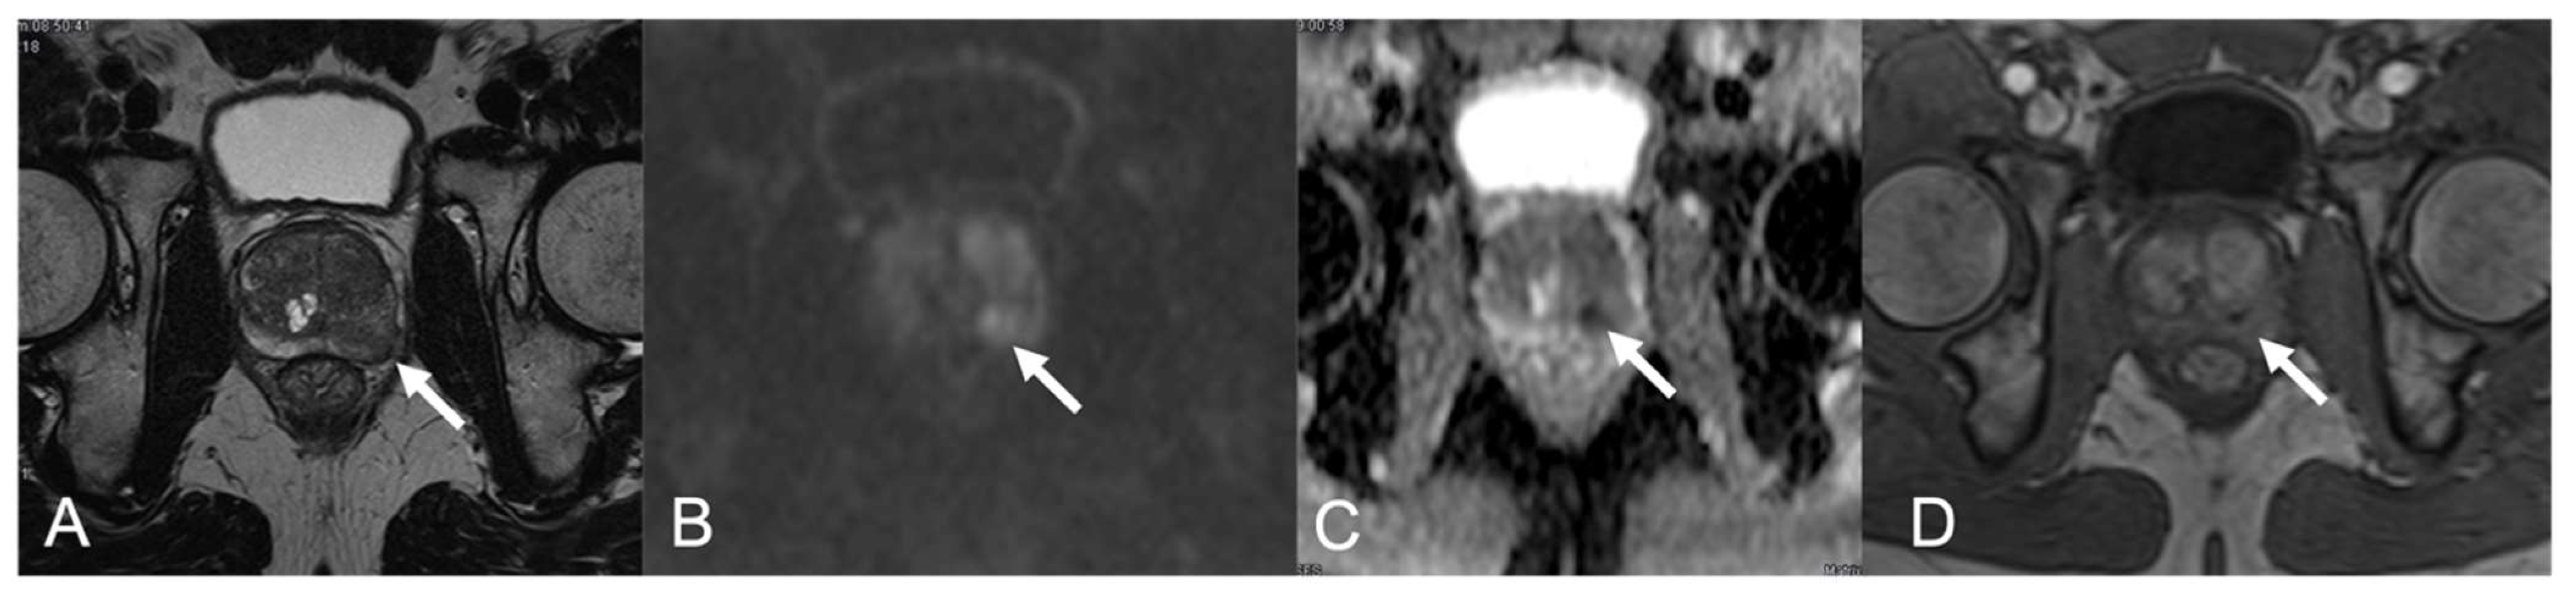

| 7 | PZa right | 0.9-cm Hypointense nodule | Mild hyperintense | Low ADC value | Hyperenhancement | 4 |

| 9 | PZ diffuse | Blurred and confluent mild hypointense areas | Hyperintense | Low ADC value | Scarce enhancement | 4 |

| 10 | PZpm right | 1.3-cm mild hypointense nodule | Hyperintense | Low ADC value | Early enhancement, high peak | 4 |

| 11 | PZpm mid-left | Hypointense nodule | Mild hyperintense | Low ADC value | High and early enhancement, high peak, early wash-out | 4 |